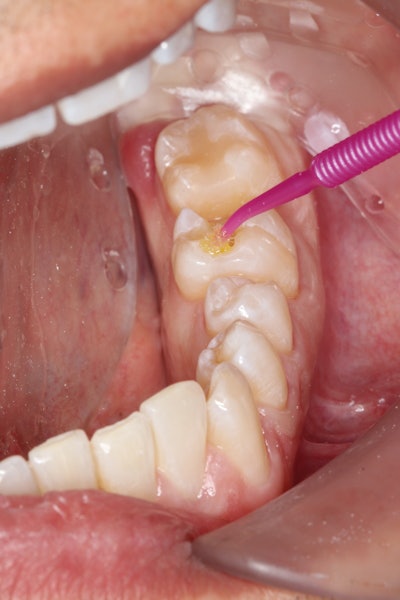

After the patient was anesthetized, isolation was obtained using the Isolite system (Zyris). The old restoration was removed, and the preparation was refined to eliminate any undercuts and decay, as well as ensure that it would draw. Following removal of the old restoration, a fine diamond (Red Stripe) was used to refine the preparation prior to taking the digital impression.

The intaglio was then microetched at 32 pounds per square inch (psi) with 50-micron aluminum oxide particles, cleaned using 37% phosphoric acid for 5 seconds, and then steam cleaned.